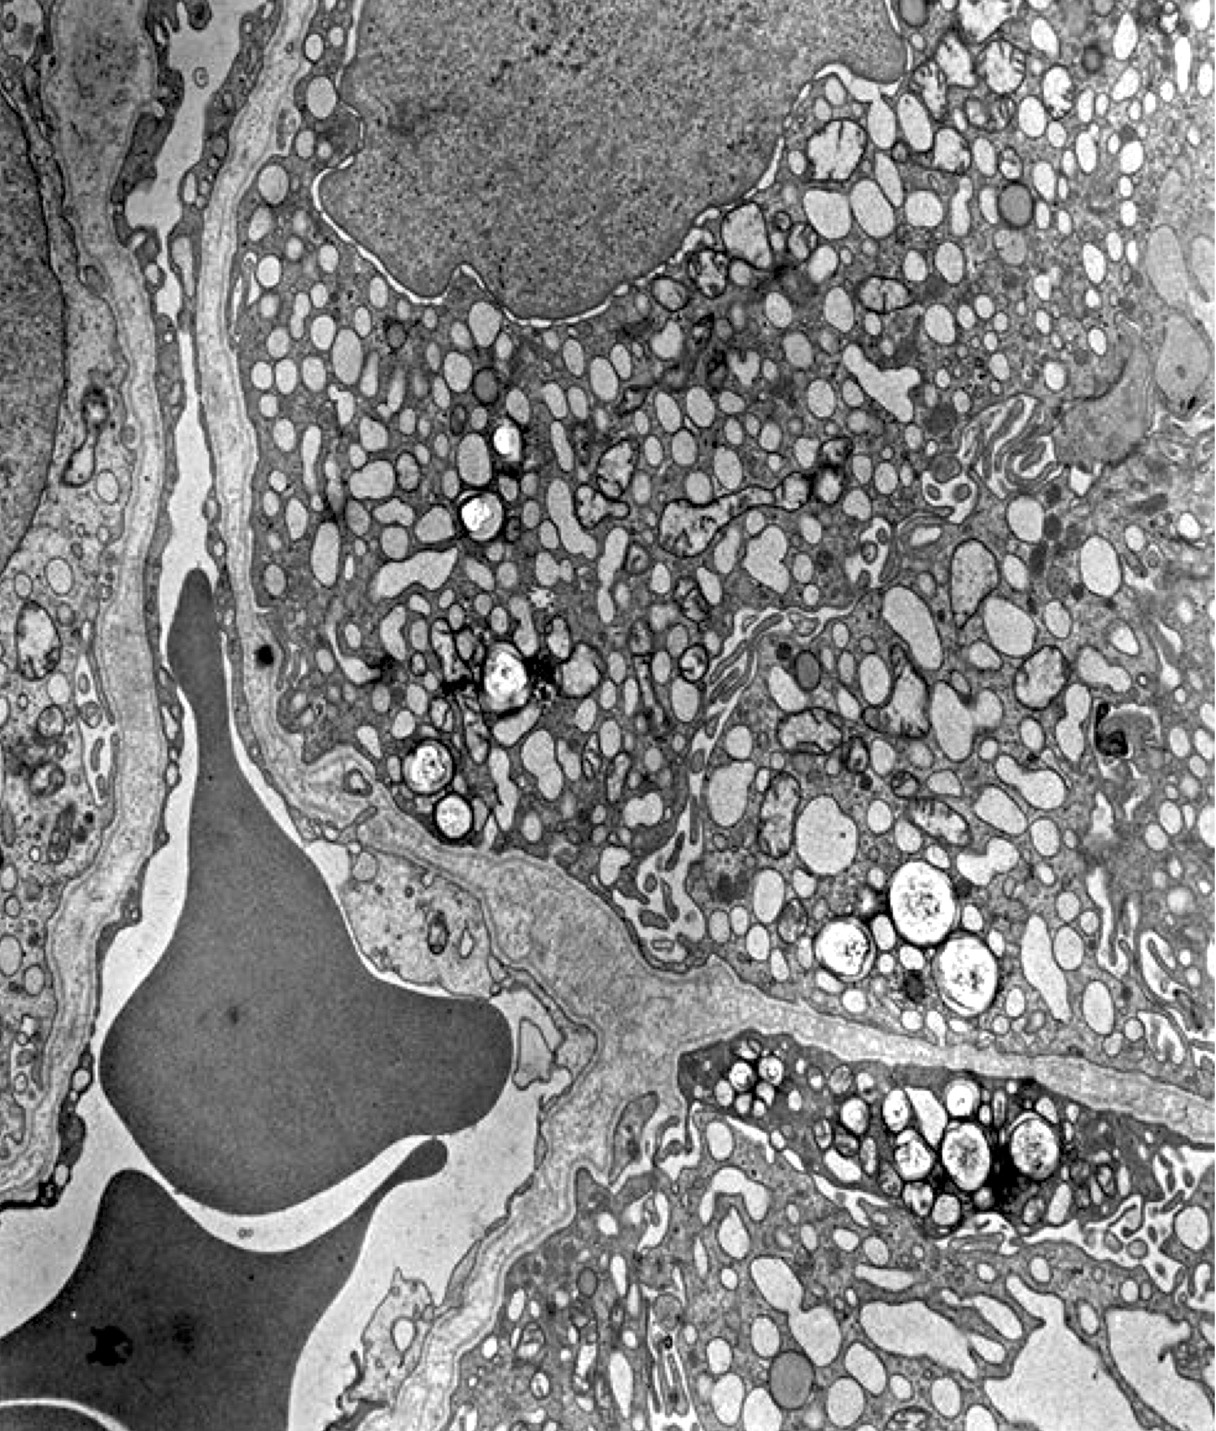

Electron microscopy description

- Similar to normal thyroid gland and hyperplastic nodules

- Hyperfunctioning follicular adenomas: organelle rich cytoplasm, especially rough endoplasmic reticulum; numerous, long microvilli on surface (Am J Clin Pathol 1982;78:299)

- Clear cell follicular adenomas: cytoplasmic vesicles of variable size; these may be dilated cisternae of the rough endoplasmic reticulum or mitochondria, lysosomes or endocytic vesicles (Virchows Arch A Pathol Anat Histol 1978;380:205)

Electron microscopy images